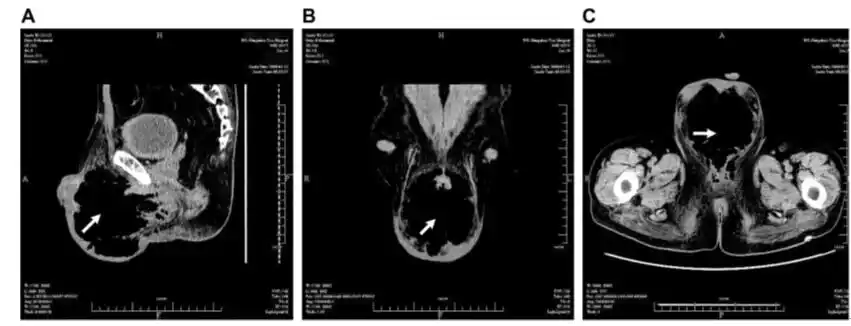

图1.(a)矢状位,(b)冠状位及(c)轴位ct扫描